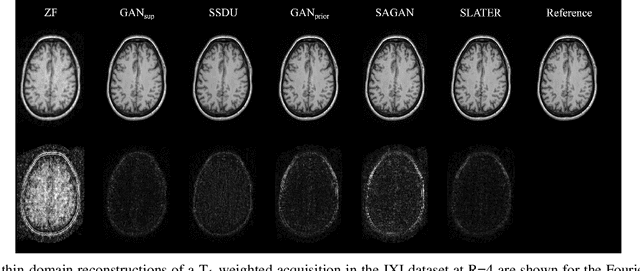

Abstract:Supervised deep learning has swiftly become a workhorse for accelerated MRI in recent years, offering state-of-the-art performance in image reconstruction from undersampled acquisitions. Training deep supervised models requires large datasets of undersampled and fully-sampled acquisitions typically from a matching set of subjects. Given scarce access to large medical datasets, this limitation has sparked interest in unsupervised methods that reduce reliance on fully-sampled ground-truth data. A common framework is based on the deep image prior, where network-driven regularization is enforced directly during inference on undersampled acquisitions. Yet, canonical convolutional architectures are suboptimal in capturing long-range relationships, and randomly initialized networks may hamper convergence. To address these limitations, here we introduce a novel unsupervised MRI reconstruction method based on zero-Shot Learned Adversarial TransformERs (SLATER). SLATER embodies a deep adversarial network with cross-attention transformer blocks to map noise and latent variables onto MR images. This unconditional network learns a high-quality MRI prior in a self-supervised encoding task. A zero-shot reconstruction is performed on undersampled test data, where inference is performed by optimizing network parameters, latent and noise variables to ensure maximal consistency to multi-coil MRI data. Comprehensive experiments on brain MRI datasets clearly demonstrate the superior performance of SLATER against several state-of-the-art unsupervised methods.